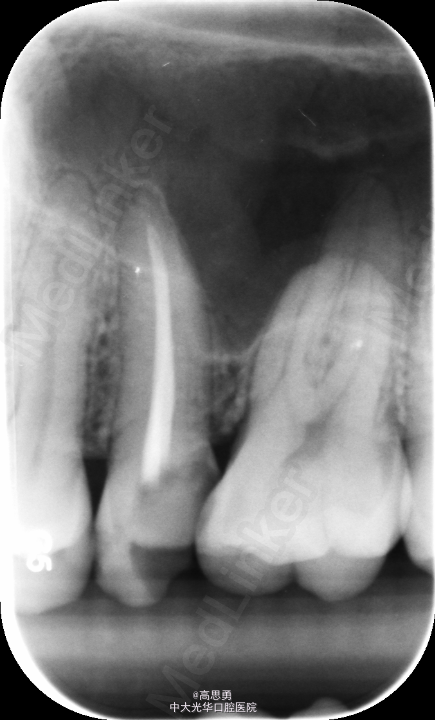

#25去腐未尽穿髓,行根管治疗。根充后X线片示:根充止点距解剖根尖孔约2mm。怀疑欠充,遂掏出牙胶后重新测量工作长度、重新根备后进行充填。第二次充填X线片与之前类似。认为可能是解剖根尖孔与生理根尖孔的差异所导致,玻璃离子暂封,观察。